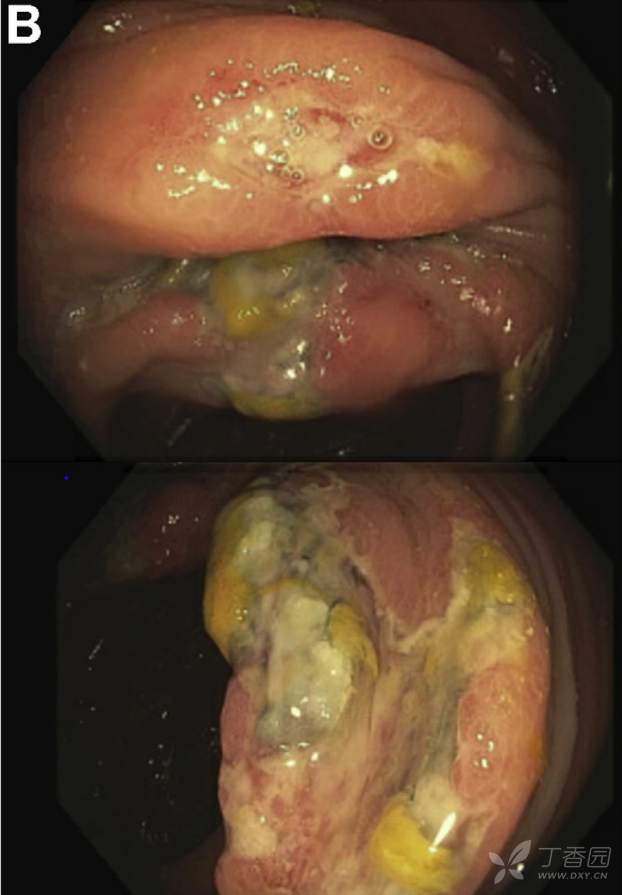

再次结肠镜检查所见升结肠(图B)。

请问:诊断是什么?

A 克罗恩病复发并累及结肠 B 结肠癌 C 肠结核 D 缺血性结肠炎